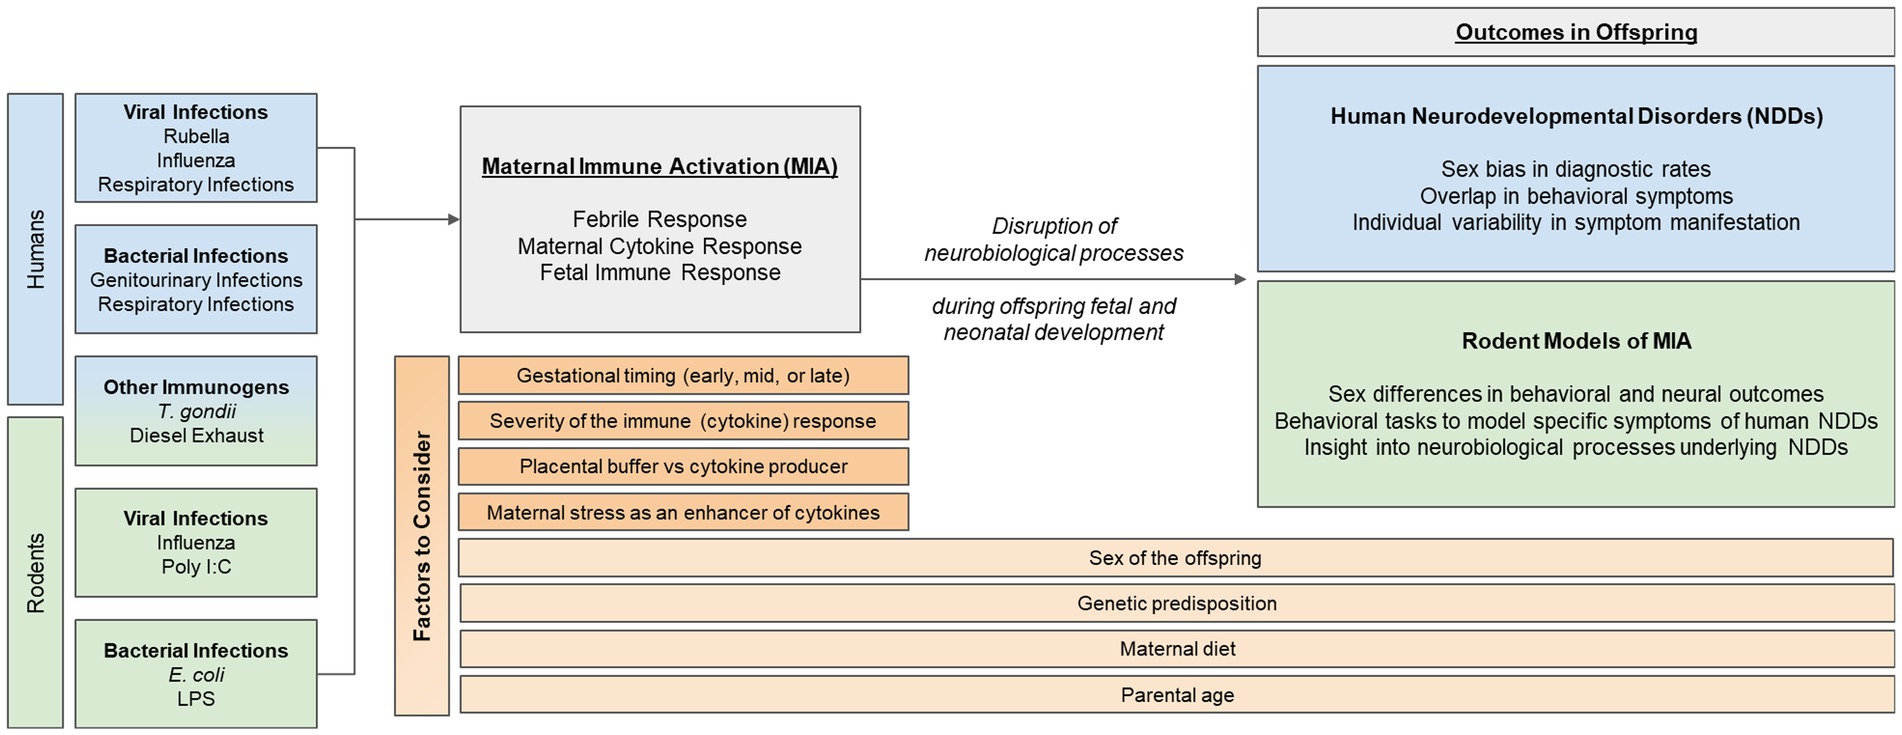

Frontiers | Maternal immune activation as an epidemiological,

Frontiers | Maternal immune activation as an epidemiological, Treatment of Budd-Chiari syndrome with inferior vena cava,